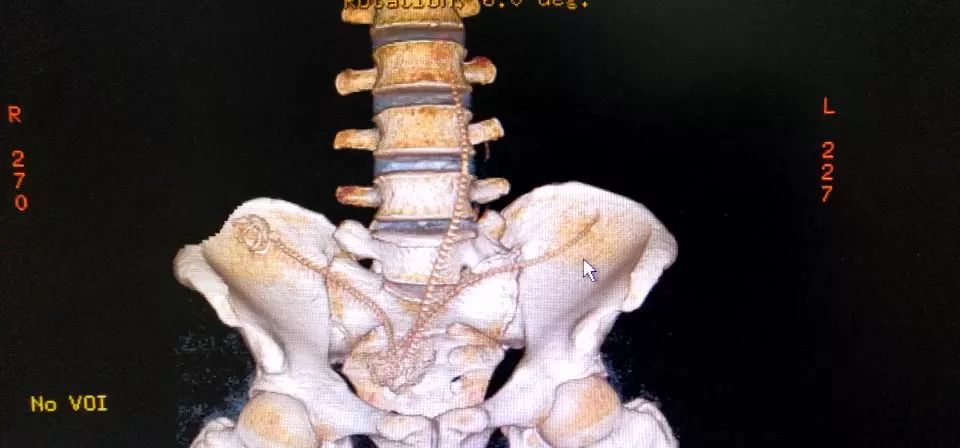

CT三维重建下三条泥鳅的骨骼清晰可见

2月10日那天我看的急诊,事情的经过是这样的,我是他的首诊大夫,一开始急诊打电话急会诊说是吃泥鳅吃坏了肚子,我觉得这也没啥,然后让他做腹部CT。后来看到他的CT赫然三条鱼骨头。我一看CT很吃惊,难道是生吃的?

去一楼急诊问患者本人,当时我听他说了事实,是下面塞进去的真把我吓一跳。他第一句话就是说,听信网上前列腺偏方把他害惨了,让我救救他赶紧手术,问我有没有穿孔,当时只有一个小时,还早,摸着板状腹很硬。他意识还有,后来就慢慢感染中毒休克了。后来术中发现乙状结肠穿孔,三条鱼都到了腹腔里,有一条还往回盲部钻,不过取出来应该都是死的了。